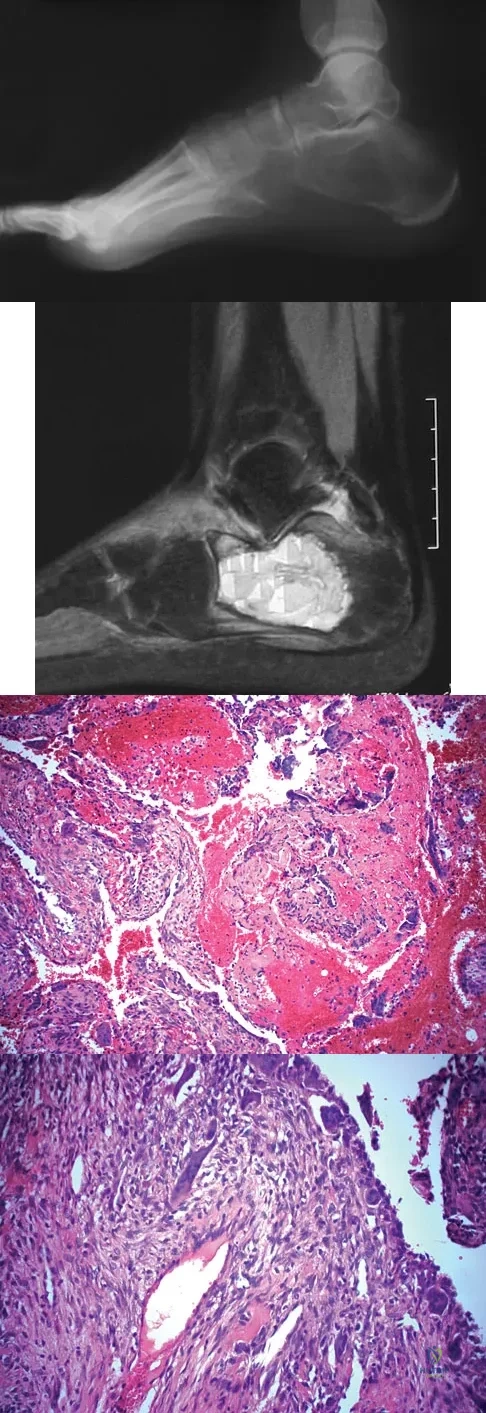

A 14-year-old girl has had progressive heel pain for the past several months. Based on the radiograph, MRI scan, and biopsy specimens shown in Figures 37a through 37d, treatment should include